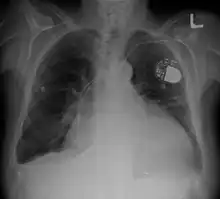

| Cardiomegaly on chest X-ray with a pacemaker | |